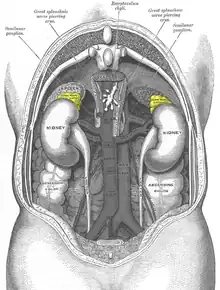

Functional imaging

The imaging modalities discussed below are for tumor characterization, confirmation of metastatic disease, and treatment planning — they are not used to discern tumor location or help the surgical team prepare for excision.[89] For most pheochromocytoma patients, functional imaging will follow a CT or MR. If anatomic imaging only demonstrates an adrenal tumor without evidence of disease anywhere else in the body and the metanephrine levels are overtly elevated, functional imaging can be foregone in favor of prompt surgical excision.[84] Over the last decade, there have been five functional techniques used to evaluate the pheochromocytoma patient (1) 18F-fluorodeoxyglucose positron emission tomography (18F-FDG PET), commonly referred to as the PET scan, (2) iodine-123 meta-iodobenzylguanadine (123I-MIBG), (3) 18F-flurodihydroxyphenylalanine (18F-FDOPA),(4) 68Ga-DOTA coupled somatostatin analogs (68Ga-DOTA),(5) 11C-Hydroxy ephedrine(HED-PET). From this point forward, these imaging modalities will be referred to in their abbreviated names found in parentheses.

The first functional imaging technique utilized in pheochromocytoma patients was 123I-MIBG scintigraphy. Given the compounds similar structure to the catecholamine norepinephrine (secreted by pheochromocytomas), MIBG was well-suited for uptake by most neuroendocrine tumors.[90] Furthermore, if a patient was found to be positive on an MIBG scan, they were eligible for MIBG treatment, offering additional avenues for those with widespread metastatic disease.[91] However, further investigation revealed that while MIBG excelled with adrenal lesions, it was far less superior in patients with extra-adrenal paragangliomas, particularly with specific genetic variants like those in the succinate dehydrogenase subunit–encoding genes (SDHx).[80] As the positron emission tomography scans were developed, MIBG has slowly lost its favor for the pheochromocytoma patient.[80]

Of the four above mentioned modalities, 18F-FDG PET is the most common and readily available functional imaging technique at most hospital systems, but the least-specific to neuroendocrine tumors (Image Left). In 2012, over 200 patients participated in a trial that compared the current gold standard of the time (MIBG/CT/MRI) to the novel FDG PET. Compared to its functional counterpart, FDG outperformed MIBG in detecting soft-tissue and bone metastases with higher specificity in patients with biochemically active tumors.[80]